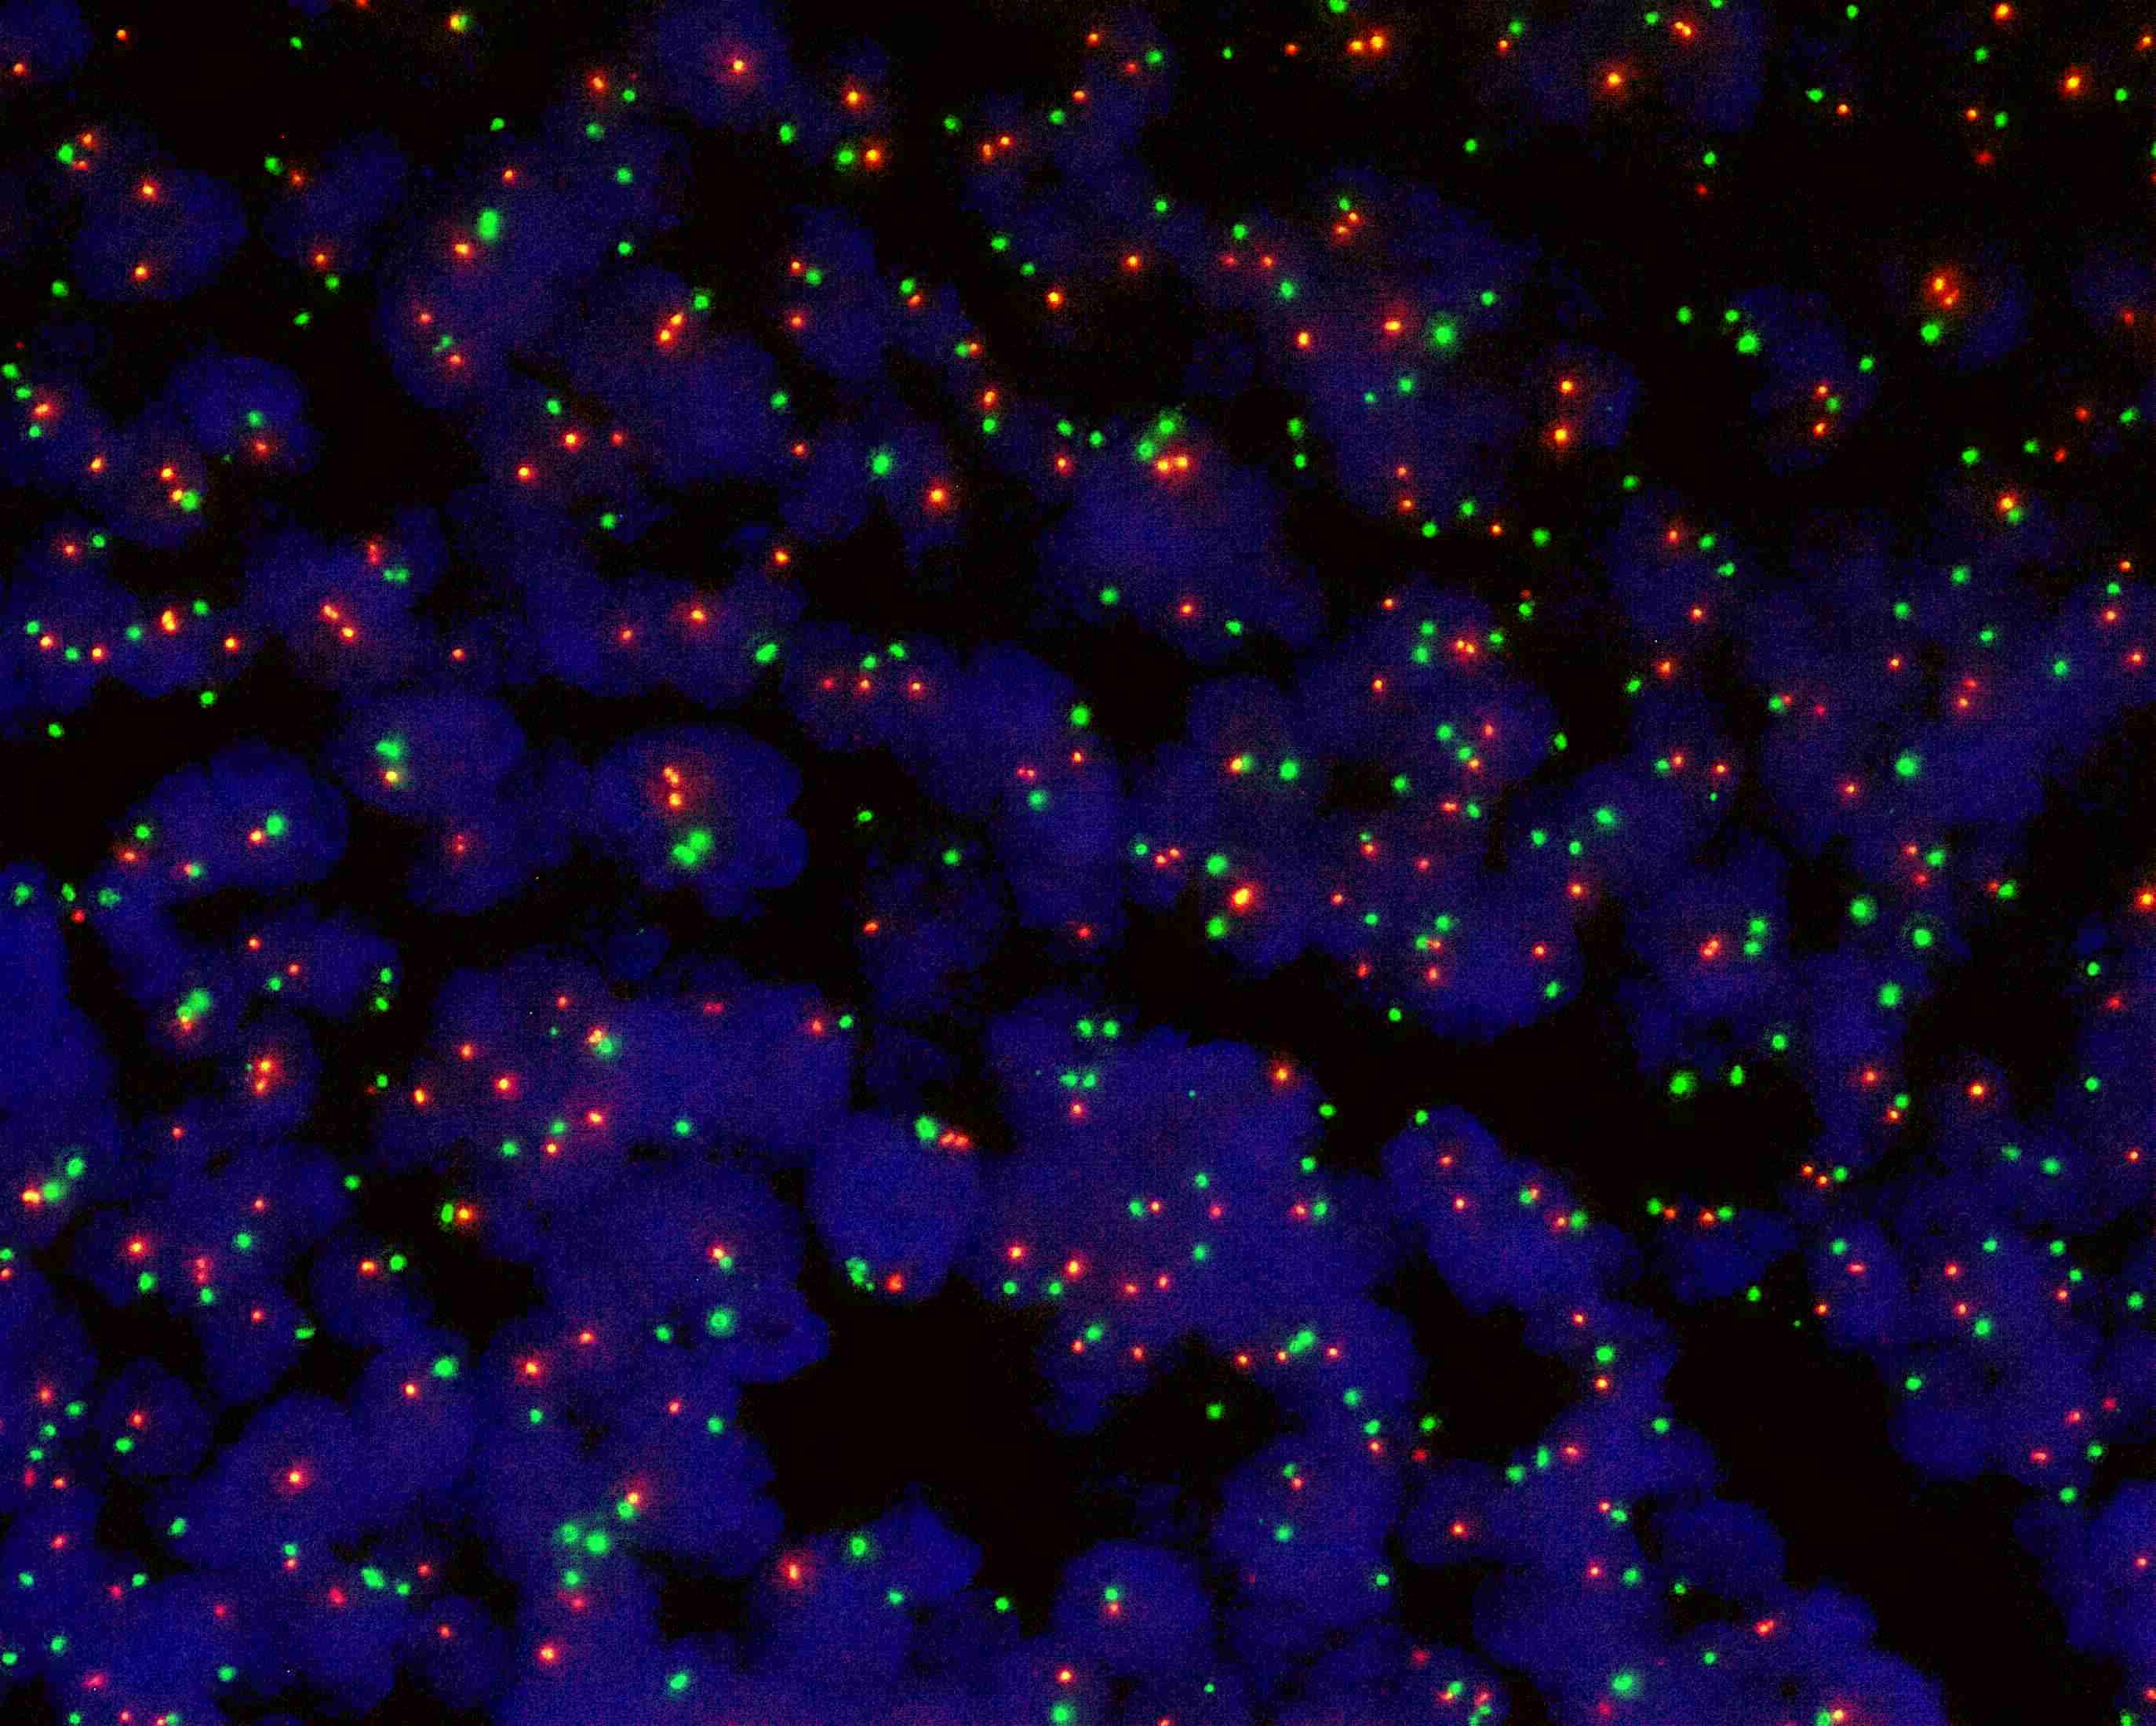

SRD (1p36) gene deletion probe reagent

SRD/PBX1 dual color probe

SRD gene (1p36) labeled as orange, with a length of 338 kb; PBX1 gene (1q23) labeled as green, with a length of 828 kb.